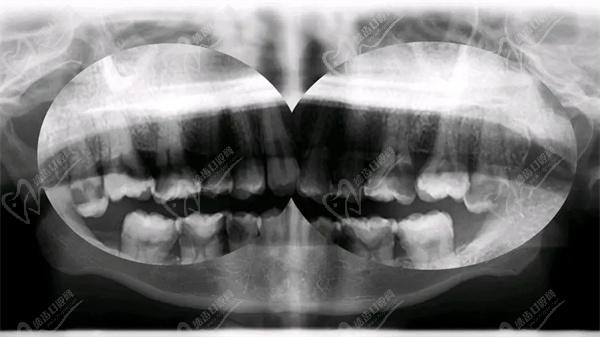

牛牙症多见于磨牙,有文献报道下颌第一前磨牙的发生率为0.4%,而下颌第2前磨牙出现牛牙症的概率更低。其他牙齿如切牙、尖牙和前磨牙等较少发生牛牙症。

诊断牛牙症主要依据临床表现和X线检查。以下是一些常用的诊断标准:

2)牙髓腔扩大:通过X线检查可以发现患者的牙髓腔明显扩大,尤其是在根尖部。

3)牙髓底部顶 端位移:X线检查显示牙髓底部向上位移,导致牙髓腔底部与牙齿顶部之间的距离增加。